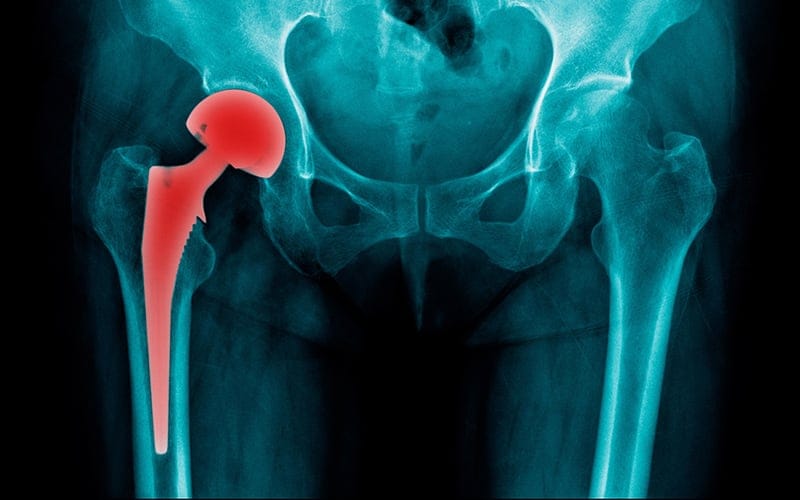

- الأشعة: إذا كان الطبيب لديه شك أن هذا الالتهاب ناتج عن وجود كسر أو التعرض لأي إصابة يطلب من المريض عمل الأشعة السينية وكذلك الخضوع للتصوير المقطعي المحوسب، حيث تعمل هذه الأشعة على تقييم المفصل بشكل دقيق وتحديد الحالة التي يوجد عليها.

- إذا كانت كل هذه الطرق السابقة غير ناجحة ومازال المريض يشعر بالألم، في هذه الحالة يلجأ الطبيب إلى إجراء عملية جراحية في المفصل نفسه ولكن يكون هذا القرار هو القرار الأخير وبعد تجربة كل الطرق السابقة.